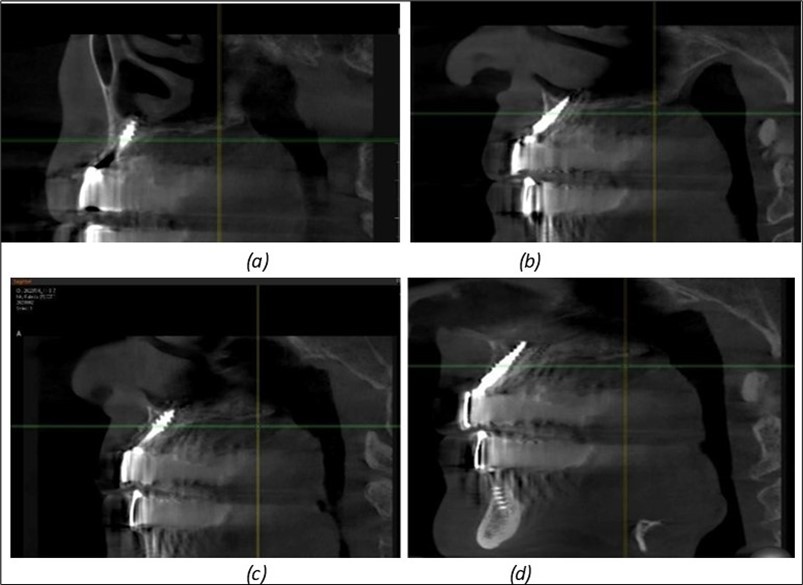

Figure 11.Implants in the anterior area anchored in the nasal cortex (BCS and TPG): (a), (c) – BCS implants fixed in the nasal cortex; (b), (d) – TPG implants fixed in the second nasal cortex with compression in the trabecular area.

Figure 12.Implants fixed distally in quadrant 4 with fixation at the level of the mylohyoid line: (a) The most distal implant fixed in unaffected bone from the previous restoration; (b) The implant fixed in the area where the two stage implant was removed.

Figure 13.Corticobasal BCS implants fixed between the vestibular and lingual cortices with support on the basal bone: (a) BCS fixed between the lateral cortices; (b) BCS implant with support on the basal cortex.